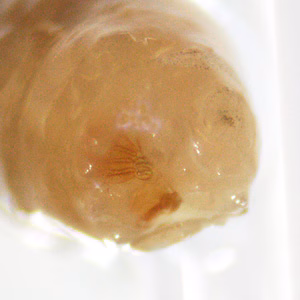

Two maggots were retrieved from a wound in an elderly woman living in rural Manitoba. Images were taken (Figures A–C) and sent to the DPDx Team for diagnostic assistance. What is your diagnosis? Based on what morphologic features?

Figure A

Figure B

Figure C

Figure D

Figure E